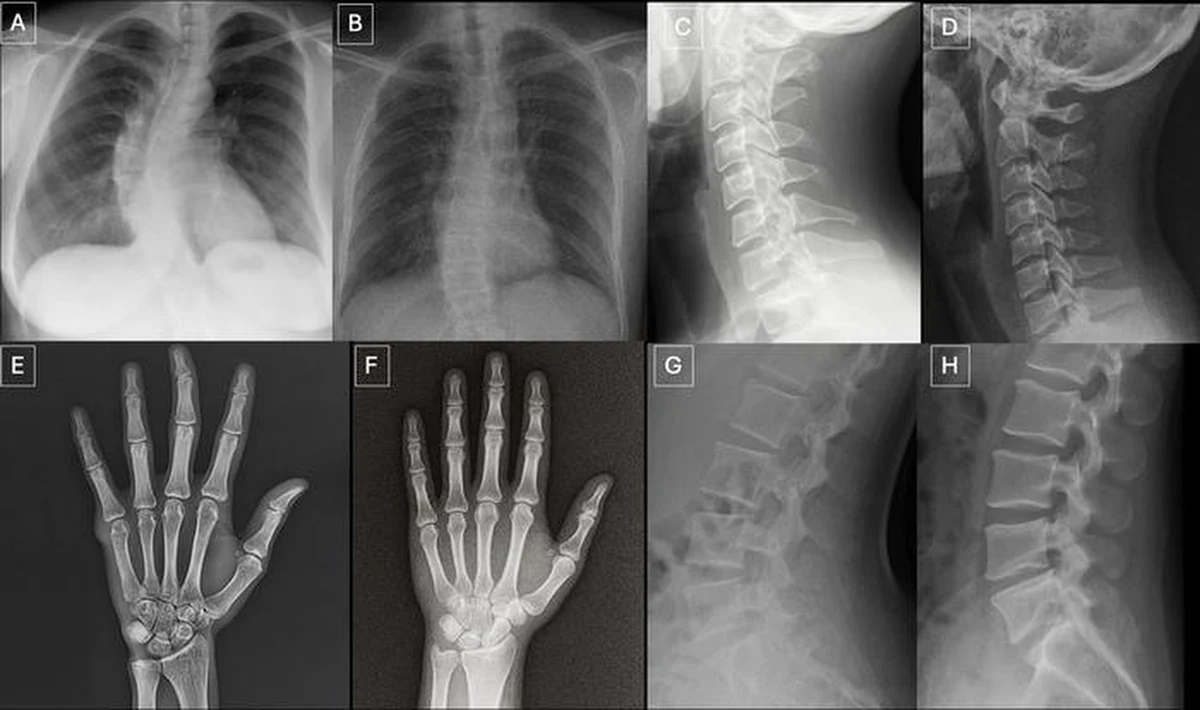

Badanie przeprowadzono na dwóch zestawach danych. Pierwszy obejmował zdjęcia różnych części ciała, zarówno prawdziwe, jak i stworzone przez model ChatGPT-4o. Drugi zestaw składał się wyłącznie z rentgenogramów klatki piersiowej, z czego połowa była autentyczna, a połowa wygenerowana przez RoentGen, model AI opracowany przez naukowców ze Stanford Medicine.

Badacze zidentyfikowali przy okazji charakterystyczne cechy fałszywek medycznych. Sztucznie wygenerowane obrazy często są "zbyt doskonałe": kości są nienaturalnie gładkie, kręgosłupy proste, płuca symetryczne, a wzory naczyń krwionośnych nadmiernie regularne. Fałszywe złamania bywają wyjątkowo czyste i ograniczone do jednej strony kości.